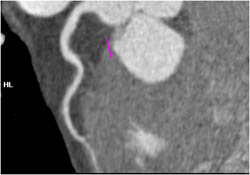

Pseudoaneurysm Near Site of Repair